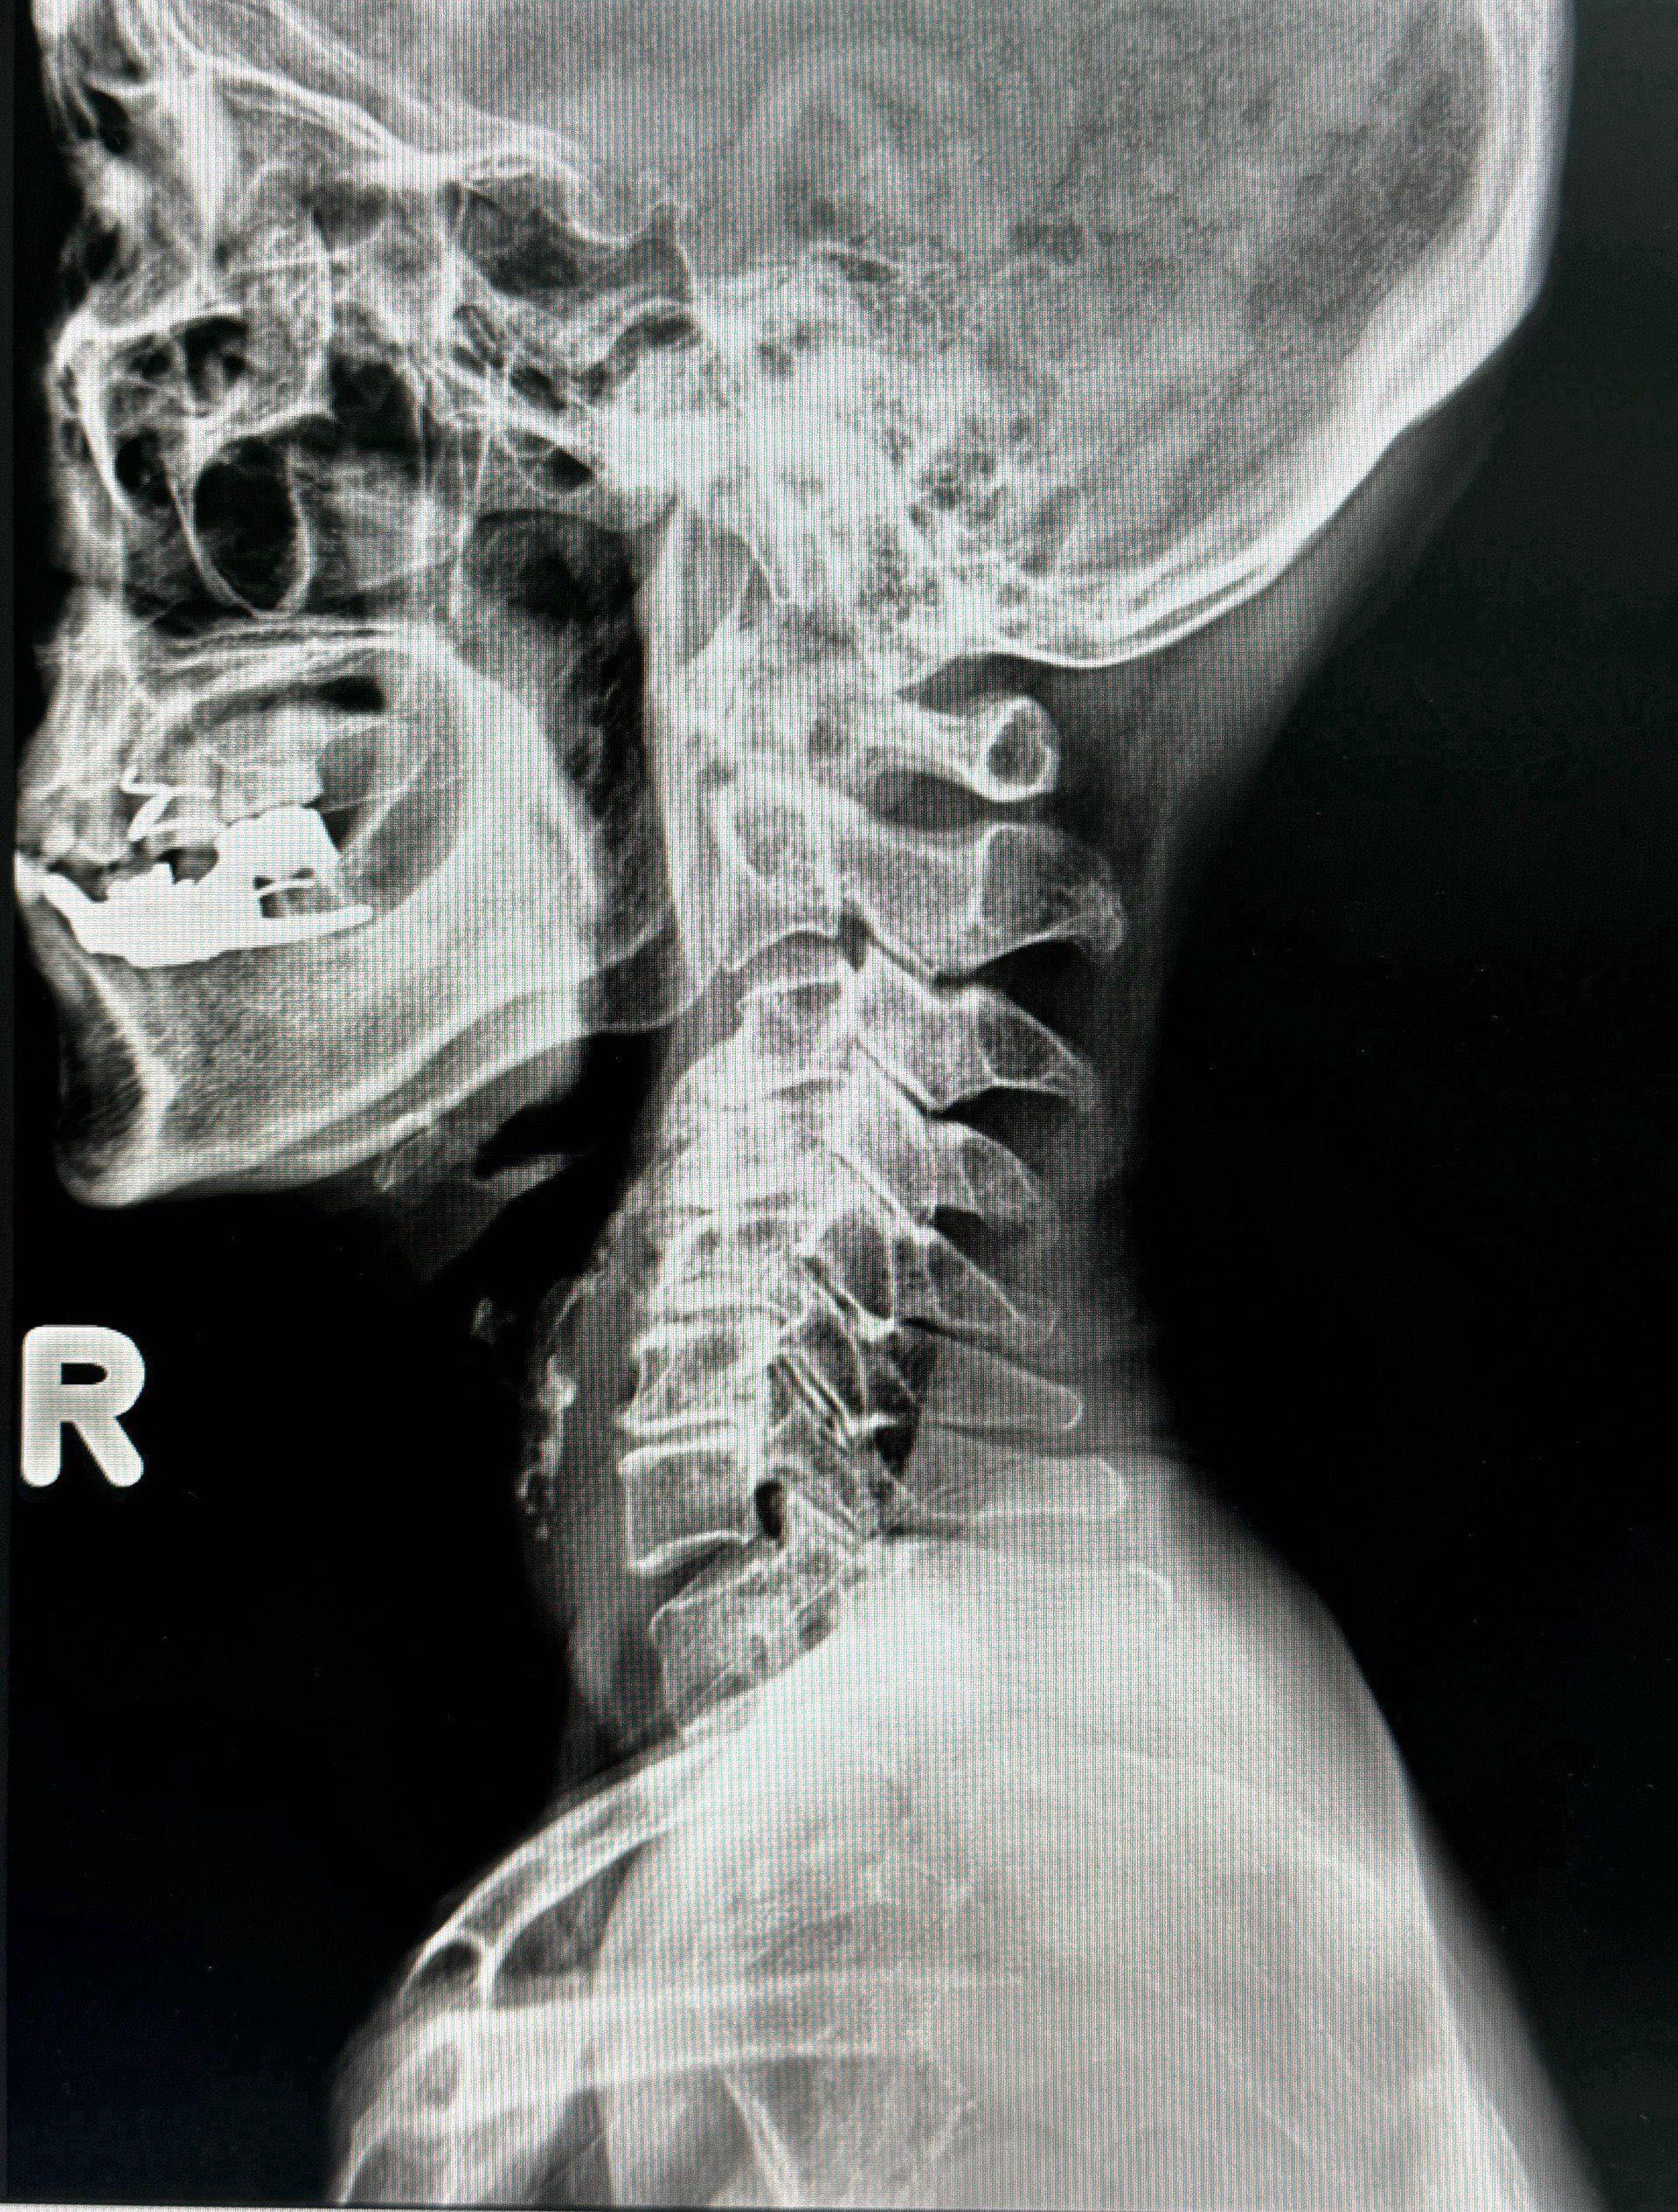

หมอนรองกระดูกคอเสื่อมเป็นปัญหาสุขภาพที่พบได้บ่อย โดยเฉพาะในคนวัยทำงานและผู้สูงอายุ หากคุณเริ่มมีอาการปวดคอเรื้อรัง รู้สึกชาหรืออ่อนแรงบริเวณแขน หรือรู้สึกไม่สบายใจเมื่อต้องเคลื่อนไหวคอ อาจถึงเวลาที่ควรหันมาให้ความสำคัญกับสุขภาพกระดูกคอมากขึ้น และรับรู้ถึงสัญญาณของหมอนรองกระดูกคอเสื่อมเพื่อตัดสินใจเข้ารับการรักษาที่เหมาะสม มารู้จักอาการเบื้องต้นกันครับ

หมอนรองกระดูกคอเสื่อมมักเริ่มต้นด้วยอาการปวดคอที่รบกวนการใช้ชีวิตประจำวัน โดยเฉพาะเมื่อคุณต้องทำงานที่เกี่ยวข้องกับการก้มคอหรือเงยคอ หากอาการปวดนี้ไม่หายไปแม้จะพักหรือเปลี่ยนท่าทาง ก็ควรตระหนักว่าอาจมีสาเหตุมาจากการเสื่อมของหมอนรองกระดูก

เมื่อหมอนรองกระดูกเสื่อม มักทำให้เกิดการกดทับเส้นประสาทบริเวณคอ ซึ่งอาจทำให้คุณรู้สึกปวดร้าวไปยังหัวไหล่ แขน หรือแม้แต่ปลายนิ้ว อาการปวดนี้ไม่ใช่เพียงอาการปวดทั่วไป แต่เป็นสัญญาณที่บ่งบอกถึงการกดทับของเส้นประสาทที่ต้องระวัง

อาการชาบริเวณแขน มือ หรือนิ้วมือ รวมถึงความรู้สึกอ่อนแรง เป็นอาการที่เกิดขึ้นเมื่อหมอนรองกระดูกกดทับเส้นประสาทที่ส่งสัญญาณไปยังแขนและมือ อาการนี้อาจทำให้คุณรู้สึกจับสิ่งของไม่ถนัด หรือรู้สึกไม่มีแรงในการบีบจับ ซึ่งจะส่งผลต่อการใช้ชีวิตประจำวันอย่างแน่นอน

การเสื่อมของหมอนรองกระดูกคอยังส่งผลให้กล้ามเนื้อบริเวณคอและไหล่ตึงเครียด คุณอาจรู้สึกปวดตึงบริเวณนี้โดยเฉพาะเมื่อทำงานหรือนั่งเป็นเวลานาน ๆ กล้ามเนื้อตึงเครียดนี้ยังทำให้การเคลื่อนไหวคอไม่คล่องตัว ซึ่งเป็นอีกสัญญาณหนึ่งของการเสื่อม

เมื่อหมอนรองกระดูกกดทับเส้นเลือดหรือเส้นประสาทบริเวณคอ อาจทำให้คุณรู้สึกเวียนศีรษะหรือเสียสมดุลได้ โดยเฉพาะเมื่อคุณเคลื่อนไหวศีรษะในทิศทางเฉพาะ อาการนี้เป็นอีกสัญญาณที่ไม่ควรมองข้าม เพราะอาจเพิ่มความเสี่ยงในการเกิดอุบัติเหตุได้

หากคุณมีอาการข้างต้นและสงสัยว่าอาจเป็นหมอนรองกระดูกคอเสื่อม การเข้ามาปรึกษาแพทย์ผู้เชี่ยวชาญเป็นสิ่งสำคัญ การวินิจฉัยที่แม่นยำและการรักษาแบบเฉพาะทาง เช่น การทำกายภาพบำบัด การฉีดยาลดอาการปวด หรือในบางกรณีที่จำเป็นอาจต้องพิจารณาการผ่าตัด จะช่วยให้อาการของคุณทุเลาลงได้อย่างมีประสิทธิภาพ